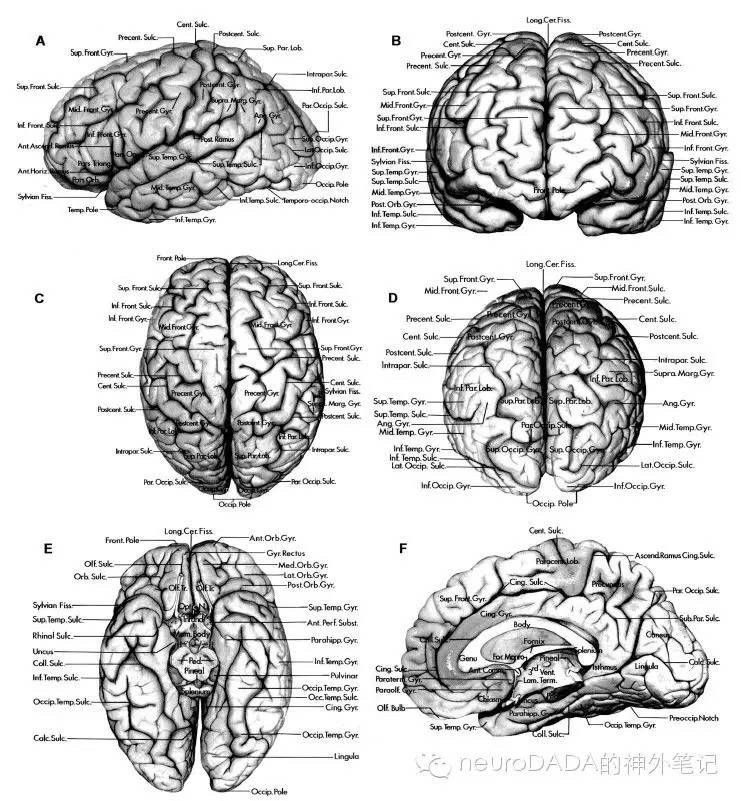

0.先看看脑沟脑回的命名

来一段教授解剖视频《 the 》的截图